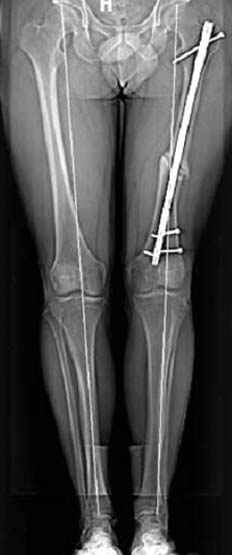

Несколько снимков из моей коллекции, чтобы разьяснить, почему мы до сих пор делаем различные варианты остеотомии.

На рисунке N1 предоперационный план лечения ложного сустава шейки бедра- линия ложного сустава, угол и направление введения импланта, клиновидная остеотомия в градусах и миллиметрах, второй снимок после коррекции, расчет, на сколько удлиняется конечность и размеры импланта;

N3 рисунок окончательный снимок, после операции моя рентгенограмма должен выглядеть примерно как эта картина. На N4 снимке клин перед удалением; N5 послеоперации 3 нед.; N6 окончательная рентгенограмма.

(доложен в Ст. Петербурге 2003 и в Москве 2004)

варус при проксимальном отделе 95 градусной пластиной.